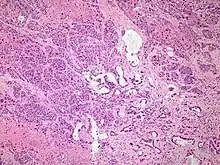

Histopathology

The most common form of pancreatic cancer (adenocarcinoma) is typically characterized by moderately to poorly differentiated glandular structures on microscopic examination. There is typically considerable desmoplasia or formation of a dense fibrous stroma or structural tissue consisting of a range of cell types (including myofibroblasts, macrophages, lymphocytes and mast cells) and deposited material (such as type I collagen and hyaluronic acid). This creates a tumor microenvironment that is short of blood vessels (hypovascular) and so of oxygen (tumor hypoxia).[11] It is thought that this prevents many chemotherapy drugs from reaching the tumor, as one factor making the cancer especially hard to treat.[11][3]